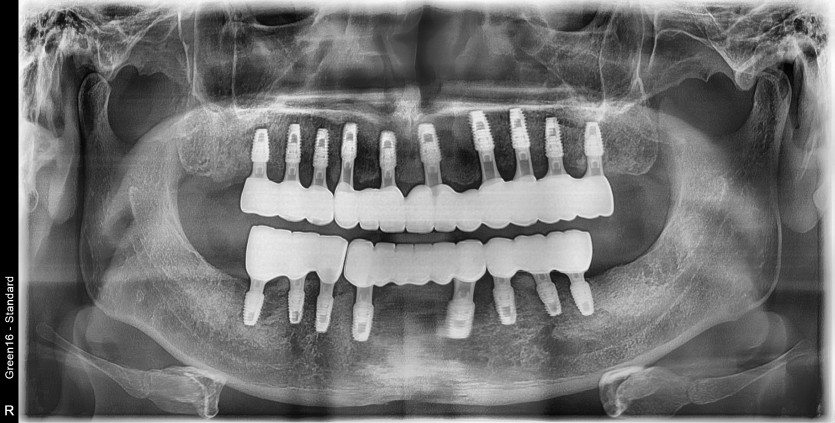

만 56세 전체 임플란트 증례

전체 임플란트 증례입니다.

18개의 임플란트로 완성하였습니다.